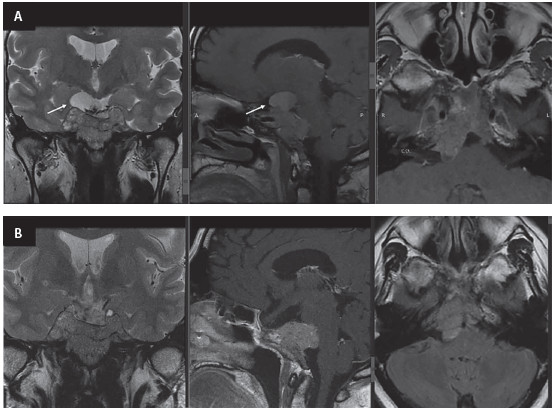

Figura 1. A. Resonancia magnética (RM) inicial (2007), corte

coronal secuencia T1: macroadenoma hipofisiario de

35 mm, componente quístico con alto contenido proteináceo y restos

hemáticos en su interior, compromiso del seno

cavernoso derecho y efecto compresivo sobre el seno cavernoso

izquierdo, contacta con el quiasma y rechaza los

nervios ópticos en sentido superior. B. RM (2008), corte coronal

secuencia T1 contrastado: masa selar y supraselar

lobulada, heterogénea, con un compromiso de ambos senos cavernosos. C y

D. RM (2011), corte coronal secuencia

T2 y corte sagital secuencia T1 contrastado: macroadenoma hipofisiario

que ocupa la cisterna supraselar, infiltra el

tallo hipofisiario y el hipotálamo, comprime el quiasma, infiltra los

senos cavernosos, invade los senos esfenoidales e

incluso alcanza la nasofaringe y ocupa la cisterna prepontina.

Figura 2. A. RM (2017), corte coronal secuencia T2, corte sagital

secuencia T1 contrastado, corte axial secuencia T1

contrastado: quiste dependiente de la masa, con alto contenido proteico

o hemorrágico (flecha), compromiso de los

senos cavernosos; crecimiento marcado hacia el área posterior

(cisterna, ángulo pontocerebeloso y efecto compresivo

sobre el puente en el lado derecho). B. RM (2018), corte coronal

secuencia T2, corte sagital secuencia T1 contrastado,

corte axial secuenciaFLAIR: Sin evidencia del quiste en el corte

coronal (mejoría de los síntomas oculares), mayor

compromiso del puente (corte sagital) y mayor compromiso hacia la fosa

posterior (corte axial).